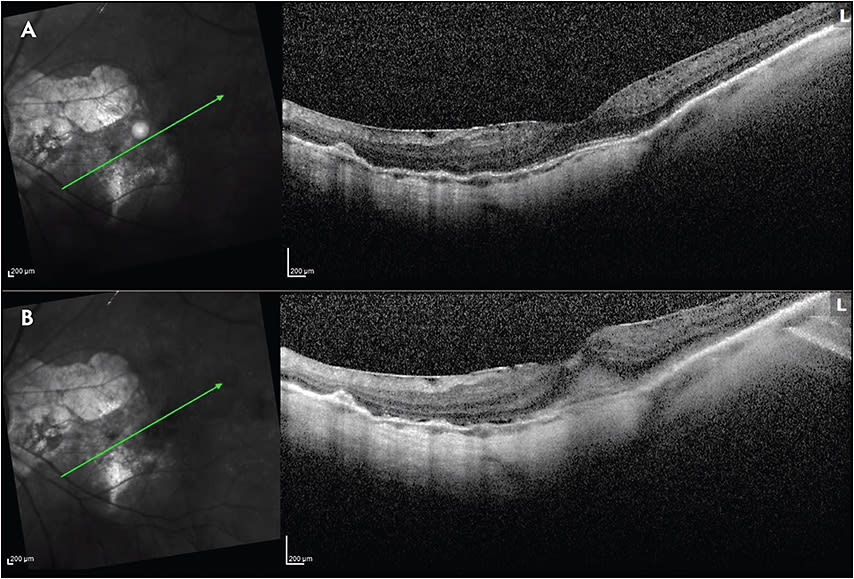

Nonadherence to recommended care similarly affects outcomes in PDR patients (Figure 2). A series of 76 eyes from 59 patients with PDR were reviewed after a 6-month gap and subsequent return to the clinic. Of those patients, 20 (33.9%) had received only anti-VEGF and 39 (66.1%) had received only PRP prior to LTFU. In terms of VA, significant worsening of vision was found in both groups, but the intravitreal injection group was disproportionately affected. In the anti-VEGF group, VA changed from 20/54 at the visit before LTFU to 20/187 at the return visit (P=.001). Despite the initiation of treatment after return, VA remained significantly worse at the final visit (20/166) (P=.01, compared to the visit before LTFU). In the PRP group, VA changed from 20/53 at the visit before LTFU to 20/83 at the return visit (P=.03). However, after treatment initiation, VA rebounded to 20/58, a nonsignificant difference from the visit before LTFU (P=.38). Structurally, there was a significantly greater prevalence of DME at the return visit (P=.005) and the final visit (P=.04) in the anti-VEGF treatment group compared with the PRP group. Also, the prevalence of neovascularization of disc, neovascularization of iris, and tractional retinal detachment was significantly higher in the anti-VEGF group compared to the PRP group at the final follow-up visit (P=.005, P=.02, and P=.005, respectively). The authors concluded that eyes with PDR do worse anatomically and functionally after a period of LTFU, particularly if they had been treated exclusively with anti-VEGF injections with no prior PRP. These findings may be due to the greater durability of PRP compared to anti-VEGF agents. It is plausible that anti-VEGF agents’ protective effect is dependent on adherence to follow-up because these drugs have a limited duration of effect.14 Although randomized clinical trials in PDR patients have established noninferiority of visual outcomes of anti-VEGF injections compared to PRP at 1 year15 and 2 years,16 achieving these results in a real-world setting is highly dependent on strict adherence to follow-up visits.